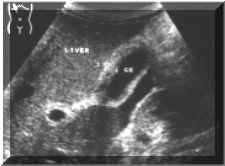

Symmetric

(Picture1)

Picture

Asymmetric